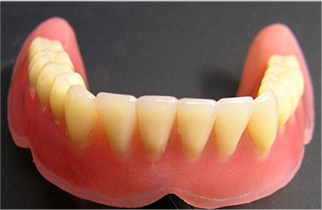

歯を失ってしまった場合に使用される入れ歯ですが、合わずにしっかりと噛むことができない入れ歯を使われている方も少なくありません。

咬み合わせは口腔内だけではなく全身に影響していきます。

口腔内の状態は日々変化しますので、現在使用中の方も、これから使用を検討されている方も、一度当院までご相談ください。

歯ぐきとの接着面が金属でできている入れ歯です。薄いため装着時の違和感が少なく、熱伝導性が高いため食べ物の温度を感じやすく、お食事も楽しんでいただけます。

165,000円~300,000円

歯ぐきとの接着面がシリコンでできており、その柔軟性が歯ぐきにかかる圧力を軽減し、噛んだ時の痛みを和らげます。顎への吸着性も高く、硬いものもしっかり噛むことができます。

165,000円~300,000円

入れ歯を支える金属のバネが無く、弾性の高い樹脂でできている入れ歯です。目立ちにくく、歯肉の色調と同化するため、入れ歯を装着していることもほとんど気づかれません。

55,000円~110,000円

※全て税込価格です